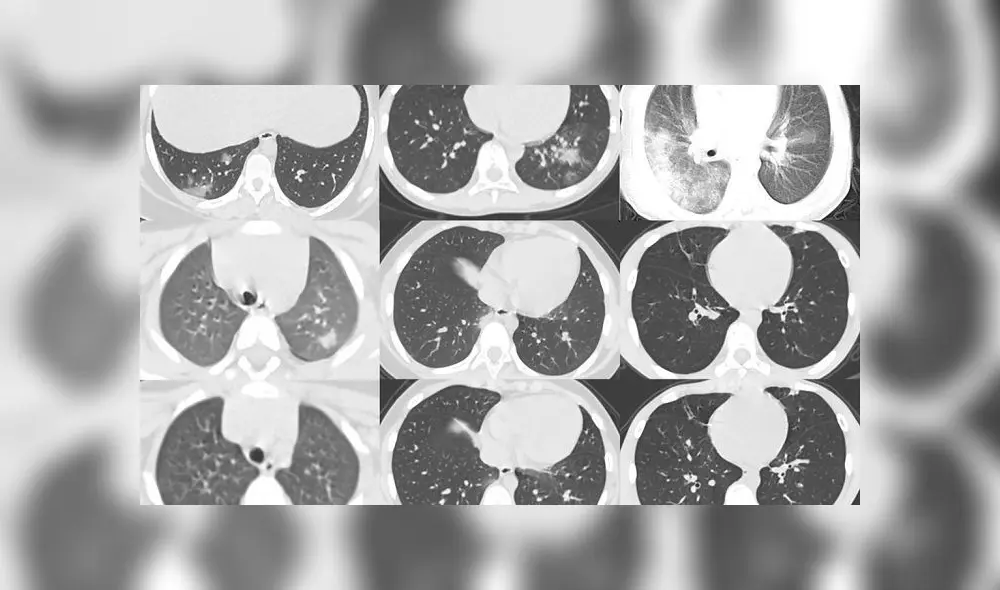

Tomografías computarizadas muestran cómo la COVID-19 puede dañar los pulmones de un niño

En Estados Unidos (EE. UU.), uno de los países que desarrolla una vacuna, un equipo de médicos del hospital infantil de Boston se enfocaron en tomografías computarizadas de casos pediátricos, refirió RT.

Su intención: desvelar cómo la enfermedad COVID-19 puede afectar los pulmones de los niños, al compararla con los daños que causan el primo del nuevo coronavirus, el SARS, la gripe de origen porcino H1N1, el uso de cigarrillos, entre otros.

Los expertos citaron un estudio publicado el 5 de marzo con tomografías computarizadas del tórax, que arrojan que casi dos tercios de los 20 niños menores de 14 años observados en Wuhan (China), tenía opacidad en vidrio esmerilado.

Opacidad en vidrio esmerilado describe el aspecto tomográfico tras el aumento de la densidad de la parénquima pulmonar, es decir, inflamación generalizada en esa zona del cuerpo.

Otro resultado fue que la mitad de los pacientes presentaban la condición llamada signo del halo, un área focal —en este caso de infección por COVID-19— redondeada con densidad de vidrio esmerilado en una masa conocida como consolidación.